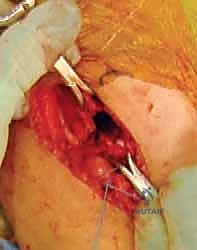

- الوصول إلى العظم: يتم إبعاد العضلات والأنسجة برفق وحذر شديد (باستخدام تقنيات الجراحة الميكروسكوبية الدقيقة عند الحاجة) لحماية الأعصاب والأوعية الدموية الحساسة في تلك المنطقة.

- الرد المفتوح (Open Reduction): إذا كان المفصل مخلوعاً بالكامل، يتم أولاً تنظيف التجويف الحُقي من أي أنسجة ليفية أو دهنية تعيق عودة رأس الفخذ، ثم يتم إرجاع رأس الفخذ إلى مكانه الطبيعي.

- القطع العظمي (The Osteotomy): يتم استخدام منشار جراحي دقيق أو أزاميل خاصة لإجراء قطع أفقي في عظم الحوض (فوق التجويف الحُقي مباشرة، من الشق الوركي الكبير إلى الشوكة الحرقفية الأمامية السفلية).